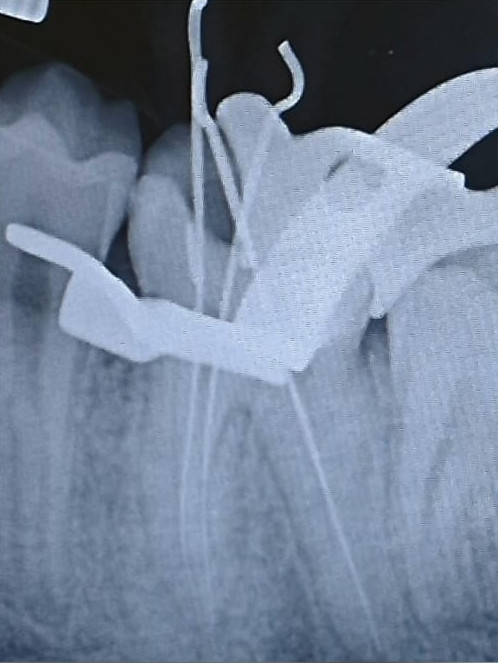

Caso Clinico

Restauri in composito

Il restauro di un dente cariato o fratturato si ottiene con il composito. È un materiale, in uso

da circa 45 anni, che diviene tutt’uno col dente.

È innocuo al dente e all’organismo. La gran parte dei restauri ha già superato i 35 anni.

Prima

Dopo